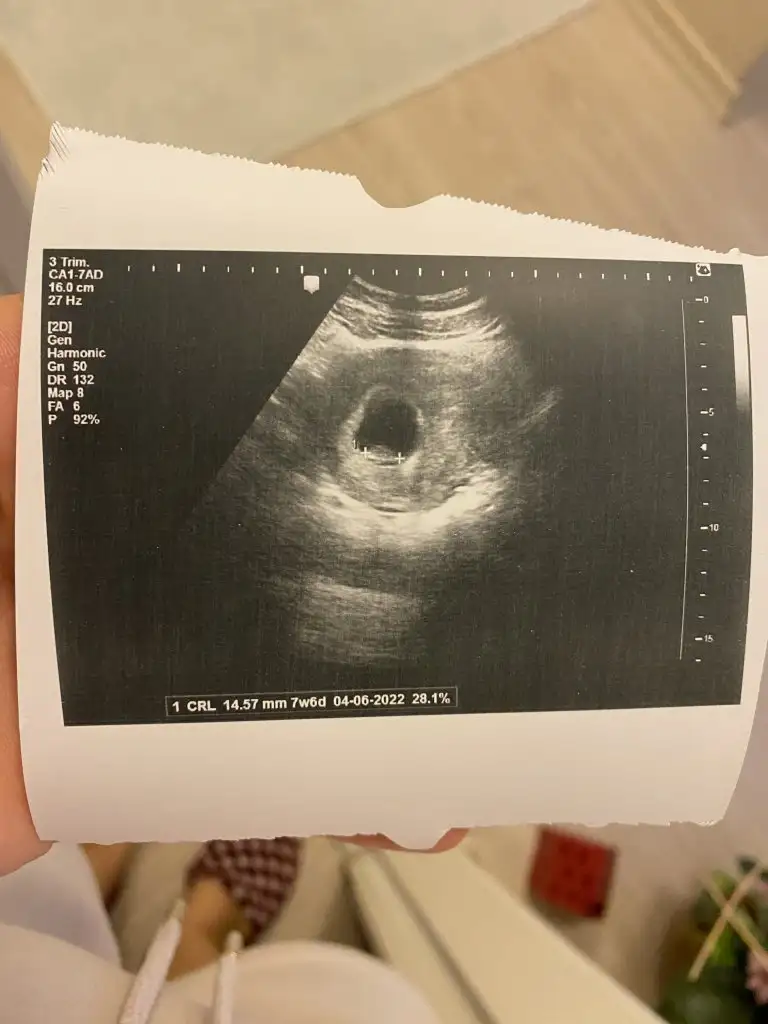

Banada ramzi tahmini yaparmisiniz karindan ultrasyon

Ramzi teorisine göre ( bilimsel bir araştırma sonucuymuş ve %85 doğruluğu varmış). İlk 6-8 haftalık ultrason görüntüsüne göre bebeğin kesenin içersinde soldan ya da sağdan girişine göre cinsiyet tahmini yapılıyor. Bilimsel olunca tecrübeli annelerimiz yada anne adaylarımızdan yardım istiyoruz. Doğruluğu var mı öğrenmek adına :) Bizleri aydınlatırsanız çok seviniriz. bu teorieye göre;

Vajinal muayeneyle bakıldıysa eğer;

Sağdan girmiş gözüküyosa aslında solmuş ve ERKEK,

Soldan girmiş gözüküyosa aslında sağmış ve KIZ ,

Karından bakıldıysa eğer,

Soldan girmiş gözüküyosa gerçektede solmuş ve ERKEK,

Sağdan girmiş gözüküyosa gerçekte de sağmış ve KIZ,

Bi teori anca bu kadar yanliş anlatilabilirdi ..arkadaşlar ramzi teorisini araştiran biri bunun doğru olmadiğini anlar ..doğru yorum yapabilmek için bebeğin konumuna gore değil plesantanin konumuna göre yorum yapılmasi gerekiyordu